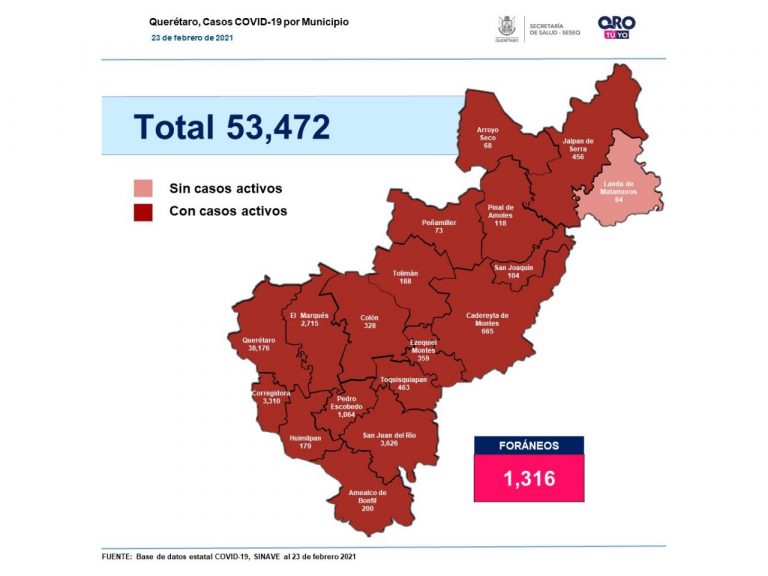

Se suman 227 casos de Covid-19 en Querétaro